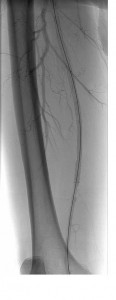

Noting both significant lesion length (~18 cm) and ostial location without calcification in our patient, we anticipated that a re-entry device might be successful (if necessary) and proceeded with antegrade probing of the CTO using an 0.035-inch angled Glidewire (Terumo, Somerset, NJ) and Seeker catheter (Bard, Tempe, AZ). As the wire could not be tracked in a straight line, we formed a loop and gently dissected subintimally to just above the knee, at which point we were able to maneuver into the reconstituted SFA.

A single 20-cm length self expanding stent was placed and post-dilated with a good result. Though a re-entry device was readily available, conventional methods proved successful in this case.